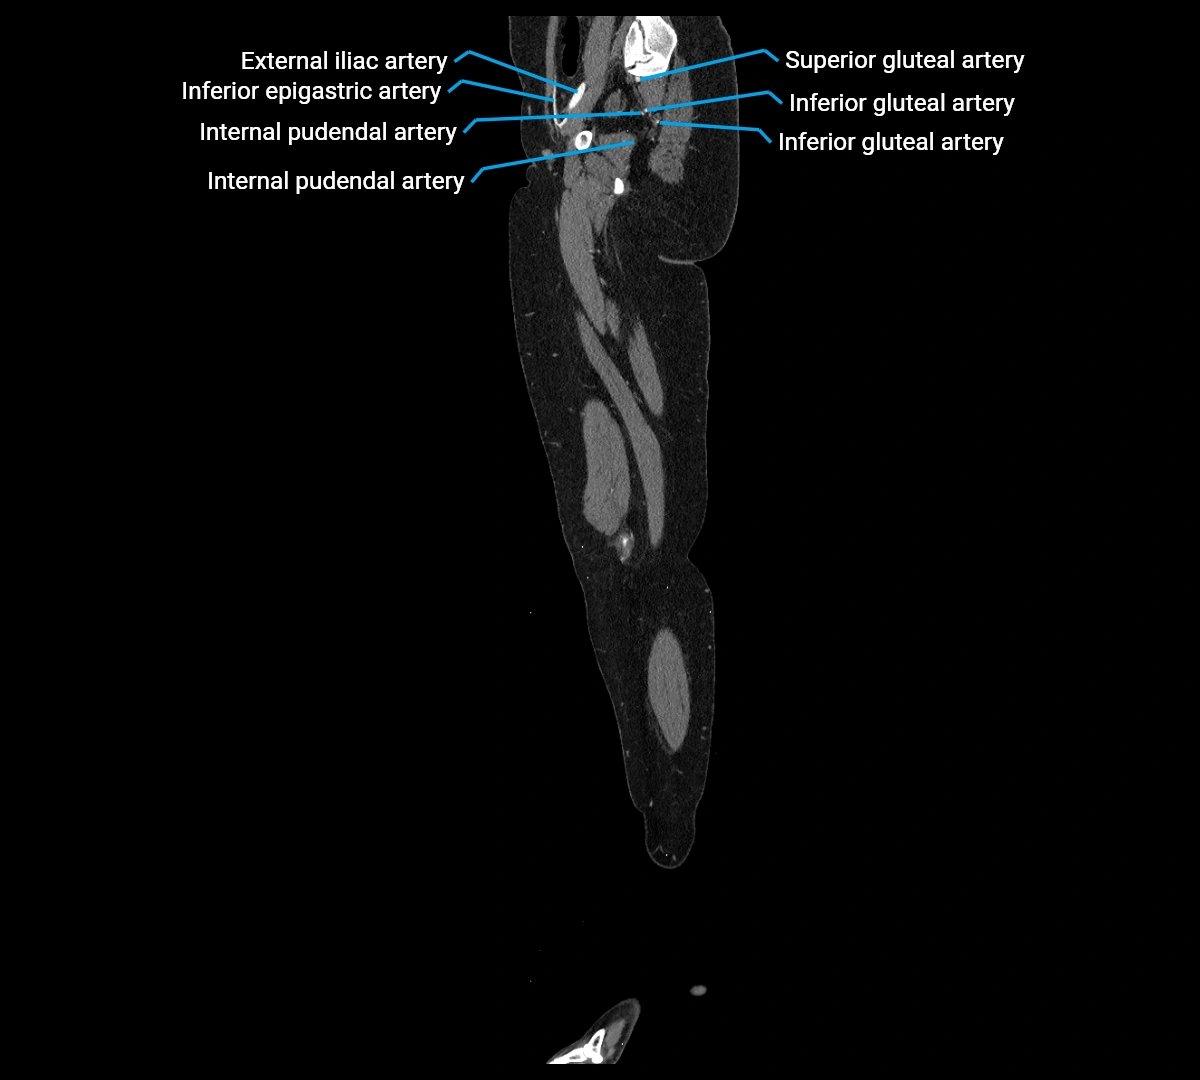

CT images

image

Contrast-enhanced CT (CTA):

• Gold standard for abdominal aortic imaging

• Provides excellent detail of lumen, wall, aneurysm, thrombus, and branch vessels

• Multiplanar and 3D reconstructions help in aneurysm measurement, stent graft planning, and dissection evaluation